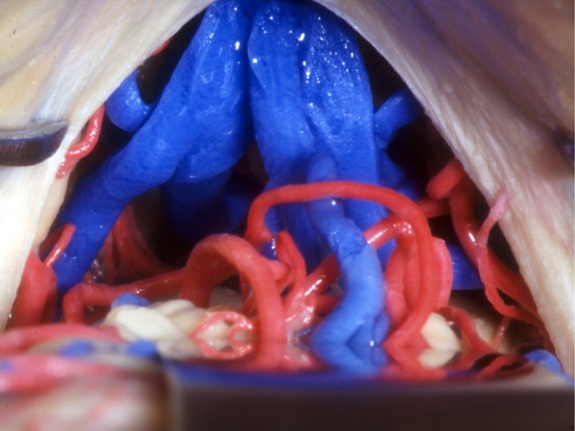

La gran estructura azul muestra a la vena cerebral magna que drena sangre desde el cerebro también conocida como “la vena de Galeno”, llamada así por el antiguo médico griego, Galeno, que la descubrió. La hipófisis, que produce una hormona que afecta a los patrones de sueño, también es visible aquí.

Los ventrículos laterales (cavidades que proporcionan amortiguación) y otras estructuras que rodean el tronco cerebral se pueden observar en esta imagen. El tronco cerebral controla las funciones básicas del cuerpo, tales como la respiración y la presión arterial. También sirve como un importante hub: Las neuronas responsables de transmitir información sensorial y motora entre el cerebro y el cuerpo viajan a través del tronco cerebral.